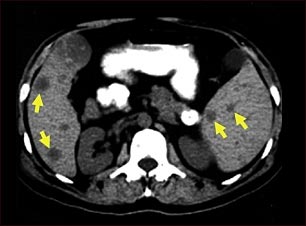

Tomografía computarizada de metástasis del bazo

Esta TC del abdomen superior muestra múltiples tumores en el hígado y el bazo que provienen (son metástasis) de un cáncer (carcinoma) intestinal original.